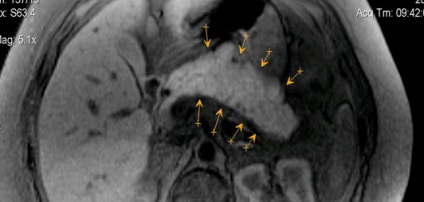

A képen - pseudotumor formájában krónikus pancreatitis